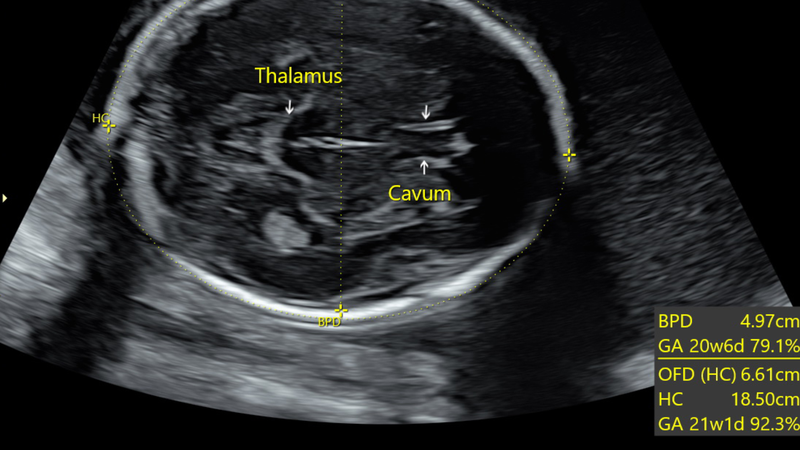

Chỉ số BPD trong siêu âm thai là gì, đây là vấn đề được nhiều mẹ bầu quan tâm. Trong thai kỳ, siêu âm là phương pháp quan trọng giúp theo dõi sức khỏe thai nhi và hỗ trợ bác sĩ đưa ra chẩn đoán, đánh giá thai phát triển. Một trong những chỉ số quan trọng được sử dụng để đánh giá kích thước đầu thai nhi là BPD (Biparietal Diameter) - đường kính lưỡng đỉnh.

BPD được đo từ mặt cắt lớn nhất của trán ra sau gáy hộp sọ thai nhi, giống như đường kính đầu của bé. Nhiều người thường nhầm lẫn BPD với HC (Head Circumference) - chu vi đầu, tuy nhiên hai chỉ số này hoàn toàn khác nhau. BPD chỉ đo đường kính, trong khi HC đo chu vi vòng đầu thai nhi.

Chỉ số BPD (Biparietal Diameter) - đường kính lưỡng đỉnh là một thước đo quan trọng trong việc theo dõi sự phát triển của thai nhi, đặc biệt là sự phát triển của não bộ. Việc đo BPD được thực hiện bằng phương pháp siêu âm, thường bắt đầu từ tuần thứ 13 của thai kỳ.

Các nghiên cứu đã chỉ ra rằng, độ chính xác của phép đo BPD cao nhất trong khoảng tuần 13 đến 20 thai kỳ. Sau giai đoạn này, do đầu thai nhi phát triển nhanh và thay đổi hình dạng, độ chính xác của phép đo có thể giảm đi.